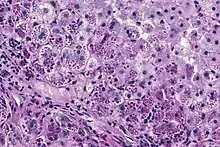

A1AT is produced in the liver, and one of its functions is to protect the lungs from neutrophil elastase, an enzyme that can disrupt connective tissue.[7] Normal blood levels of alpha-1 antitrypsin may vary with analytical method but are typically around 1.0-2.7 g/l.[12] In individuals with PiSS, PiMZ and PiSZ genotypes, blood levels of A1AT are reduced to between 40 and 60% of normal levels; this is usually sufficient to protect the lungs from the effects of elastase in people who do not smoke. However, in individuals with the PiZZ genotype, A1AT levels are less than 15% of normal, and they are likely to develop panlobular emphysema at a young age. Between 10 and 15% of these people will develop liver fibrosis or liver cirrhosis, because the A1AT is not secreted properly and therefore accumulates in the liver.[13] A liver biopsy in such cases will reveal PAS-positive, diastase-resistant granules. Unlike glycogen and other mucins which are diastase sensitive (i.e., diastase treatment disables PAS staining), A1AT deficient hepatocytes will stain with PAS even after diastase treatment - a state thus referred to as "diastase resistant".